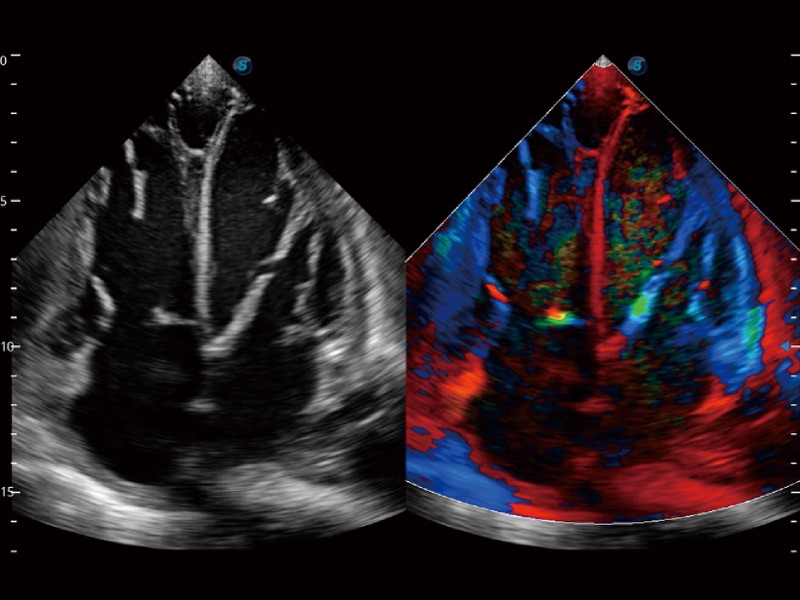

• 心血管应用

• 负荷超声心动图

支持运动和药物负荷协议、多心动周期存储选择,为临床观察心肌负荷状态下的室壁节段运动、评估心肌缺血状态提供更多的解决方案。

• 心肌定量分析 MQA

通过心肌识别技术和二维斑点追踪技术相结合,计算心肌各节段的应变应变率、速度、位移并以曲线图显示,实现整体或者局部心肌定量分析。同时可呈现牛眼图直观和准确诊断心肌的运动情况。